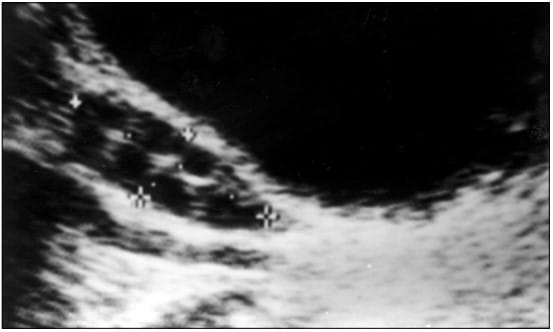

A ultrassonografia transvaginal é o principal método de imagem utilizado para a avaliação dos ovários em pacientes com suspeita de Síndrome dos Ovários Policísticos. Ela permite uma visualização detalhada da anatomia ovariana e identificação das características morfológicas que são indicativas da condição.

O exame é realizado com o paciente em decúbito dorsal, utilizando um transdutor vaginal para gerar imagens dos ovários. Essa abordagem oferece alta resolução, permitindo a contagem folicular e a avaliação do volume ovariano.

A ultrassonografia transvaginal deve ser preferencialmente realizada durante a fase folicular precoce do ciclo menstrual (dias três a dia cinco) para minimizar a influência dos folículos dominantes que podem estar em crescimento.

- Distribuição periférica dos folículos: Os folículos estão frequentemente dispostos na periferia do ovário, conferindo o aspecto clássico de “colar de pérolas” em cortes transversais.